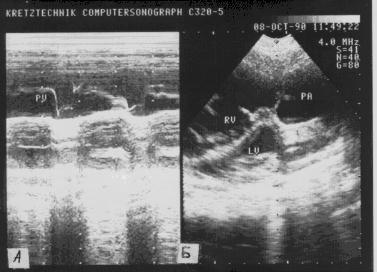

Одномерная ЭхоКГ (рис.139):

Рис.139

Эхокардиограмма при

первичной легочной

гипертензии:

небольшой

инфундибулярный

стеноз, гипертрофия и

дилатация правого

желудочка,

уменьшение полости

левого желудочка,

относительная

недостаточность

трикуспидального

клапана.

- Отсутствие или уменьшение А волны

клапана легочной артерии (при присоединении правожелудочковой недостаточности

волна вновь появляется).

- Уменьшение EF наклона створки легочной артерии (малоспецифичный

признак).

- Среднесистолическое прикрытие створки легочной артерии.

- Изменение кинетики перегородки (в раннюю систолу

перегородка движется парадоксально, затем быстро совершает заднее

движение.

- Задержка открытия клапана легочной артерии.

- Увеличение скорости открытия клапана легочной артерии.

- Пологий EF наклон передней створки митрального клапана

(при нормальном движении его задней створки).

- Гипертрофия передней стенки правого желудочка.

- Гипертрофия межжелудочковой перегородки.

- Систолическое трепетание створок клапана легочной

артерии.

- Дилатация правого желудочка.